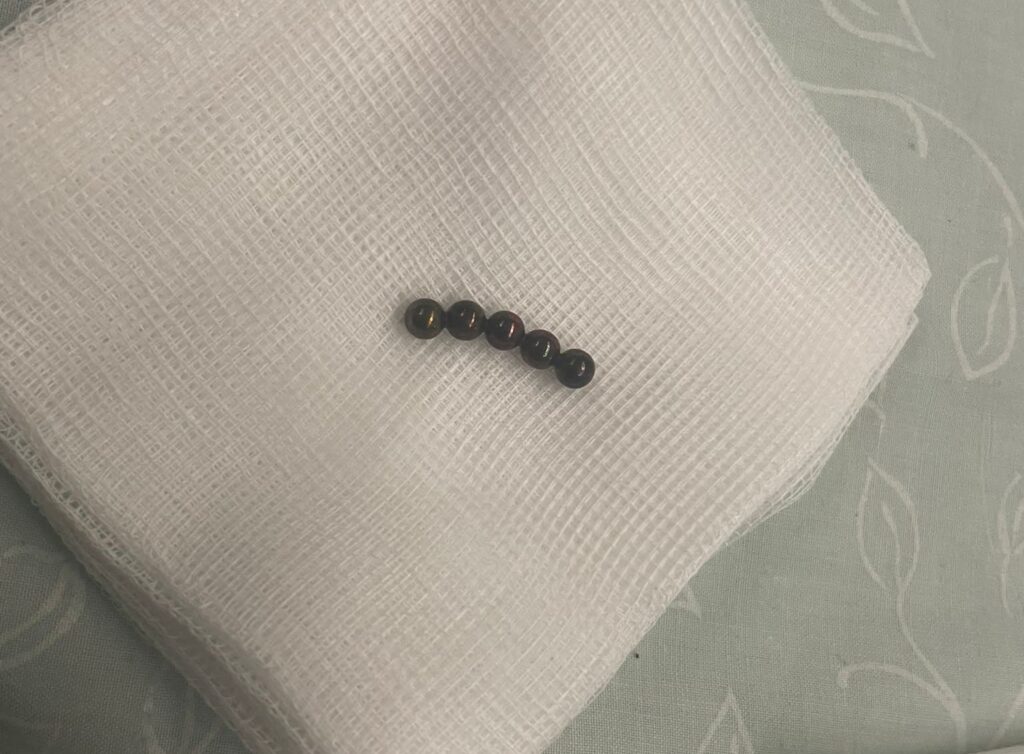

הניתוח הראשון, של הילדה בת ה 4, נעשה בראשותם של ד"ר עופר גליק וד"ר ירדן טננבאום ממחלקת א.א.ג/ניתוחי ראש צוואר; הניתוח השני, של הילדה בת ה 7, נעשה הבוקר (יום ד) על ידי ד"ר חני טאף. לשמחת כולם, הניתוחים הסתיימו בהצלחה. מטבעות הכסף וחלקי המשחק הוצאו בשלמותם והילדות הועברו להמשך טיפול והשגחה במחלקת הילדים של ביה"ח הציבורי אסותא אשדוד.